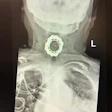

Head and Neck Radiology: Page 9